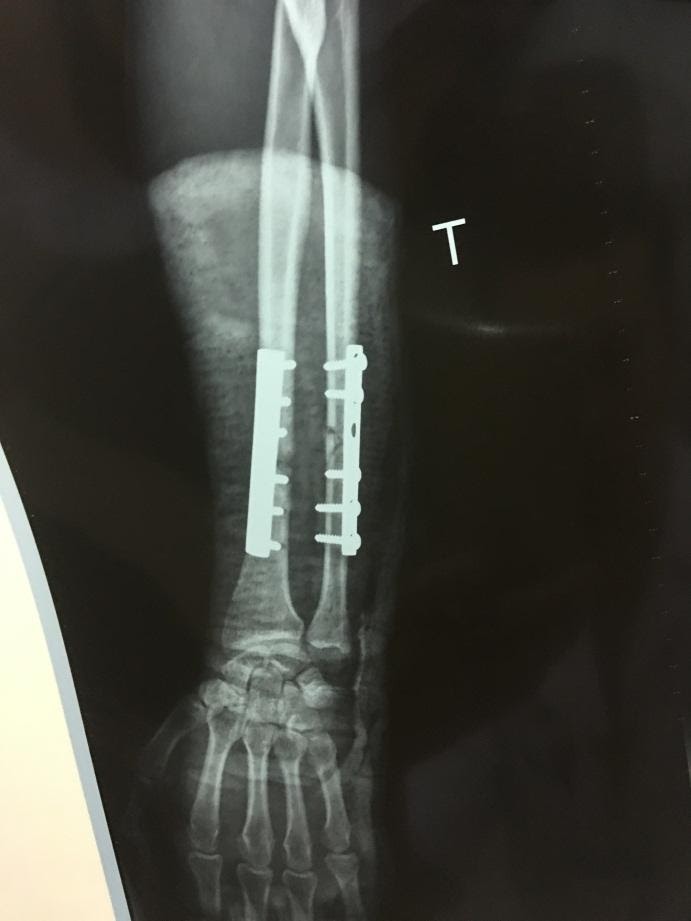

Sau khi hội chẩn đã thống nhất phẫu thuật ngay trong đêm, kết hợp xương bằng nẹp vít giúp trả lại chức năng cẳng bàn tay trái cho bệnh nhân.

Kíp phẫu thuật do Bs Bùi Xuân Sanh - TK Ngoại và các bác sĩ khoa Ngoại cùng kíp trực thực hiện. Dự kiến, bệnh nhân sẽ được xuất viện sau 4 - 5 ngày tới.

Trước phẫu thuậtSau phẫu thuật